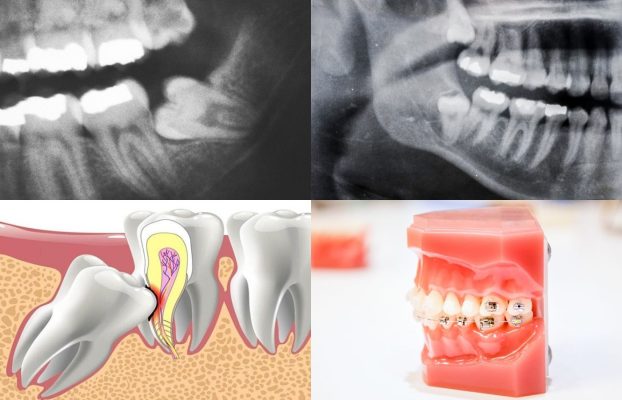

Răng khôn (răng số 8) thường mọc ở độ tuổi 17–25. Nhiều người nghĩ rằng răng khôn phải nhổ hết, nhưng không phải trường hợp nào cũng cần nhổ. Việc giữ hay nhổ phụ thuộc vào vị trí mọc và tình trạng của răng.

Mọc lệch, mọc ngang gây đau và viêm nướu

Mọc ngầm trong xương hàm

Làm sâu răng kế bên (răng số 7)

Gây chen chúc hoặc ảnh hưởng đến chỉnh nha

Không phải răng khôn nào cũng cần nhổ. Việc quyết định giữ hay nhổ cần thăm khám và chụp phim X-quang để đánh giá chính xác.